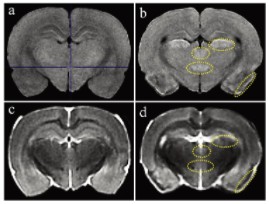

Figure 1 presents T1- and T2-weighted MRI images. Compared with controls, pilocarpine-treated rats showed high T1 signals in the piriform cortex, lateral thalamic nucleus, periventricular thalamic posterior nucleus, and hypothalamic posterior nucleus (Fig. 1a and b). In T2-weighted images, the piriform cortex exhibited low T2 signal corresponding to the high T1 area (Fig. 1c and d). The other three high-T1 regions displayed T2 intensities comparable to controls (moderate intensity) (Fig. 1c and d).

Today’s user-friendly compact small-animal MRI systems are highly applicable to preclinical toxicological pathology studies of pilocarpine-induced brain injury in rats. High T1 and low T2 signals reveal evident neuronal damage, even though histopathological analysis remains more sensitive.